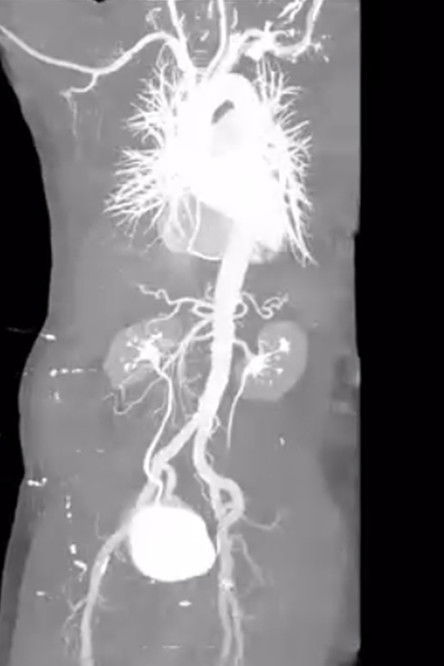

“X-ray Eros” is a short video featuring actual medical scans and imagery of the artist’s internal body taken in connection with a life-threatening stroke within the past year, involving (successful) brain surgery, and a very recent hernia surgery.